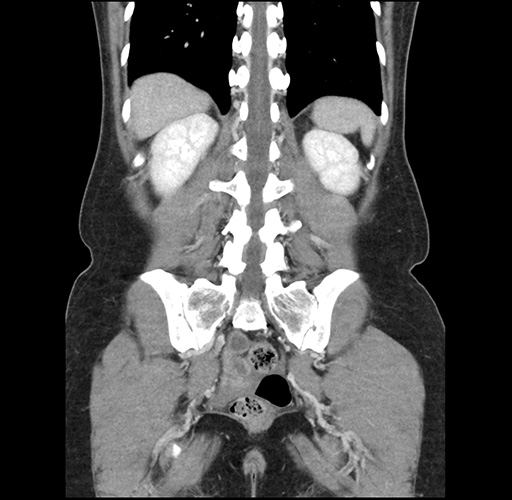

Imaging Analysis

Look through the patient's CT scan to identify any areas of concern for the necessary procedure.

Based on your CT findings, which issue(s) would give reason for "planned slowing down moment(s)" in this case?